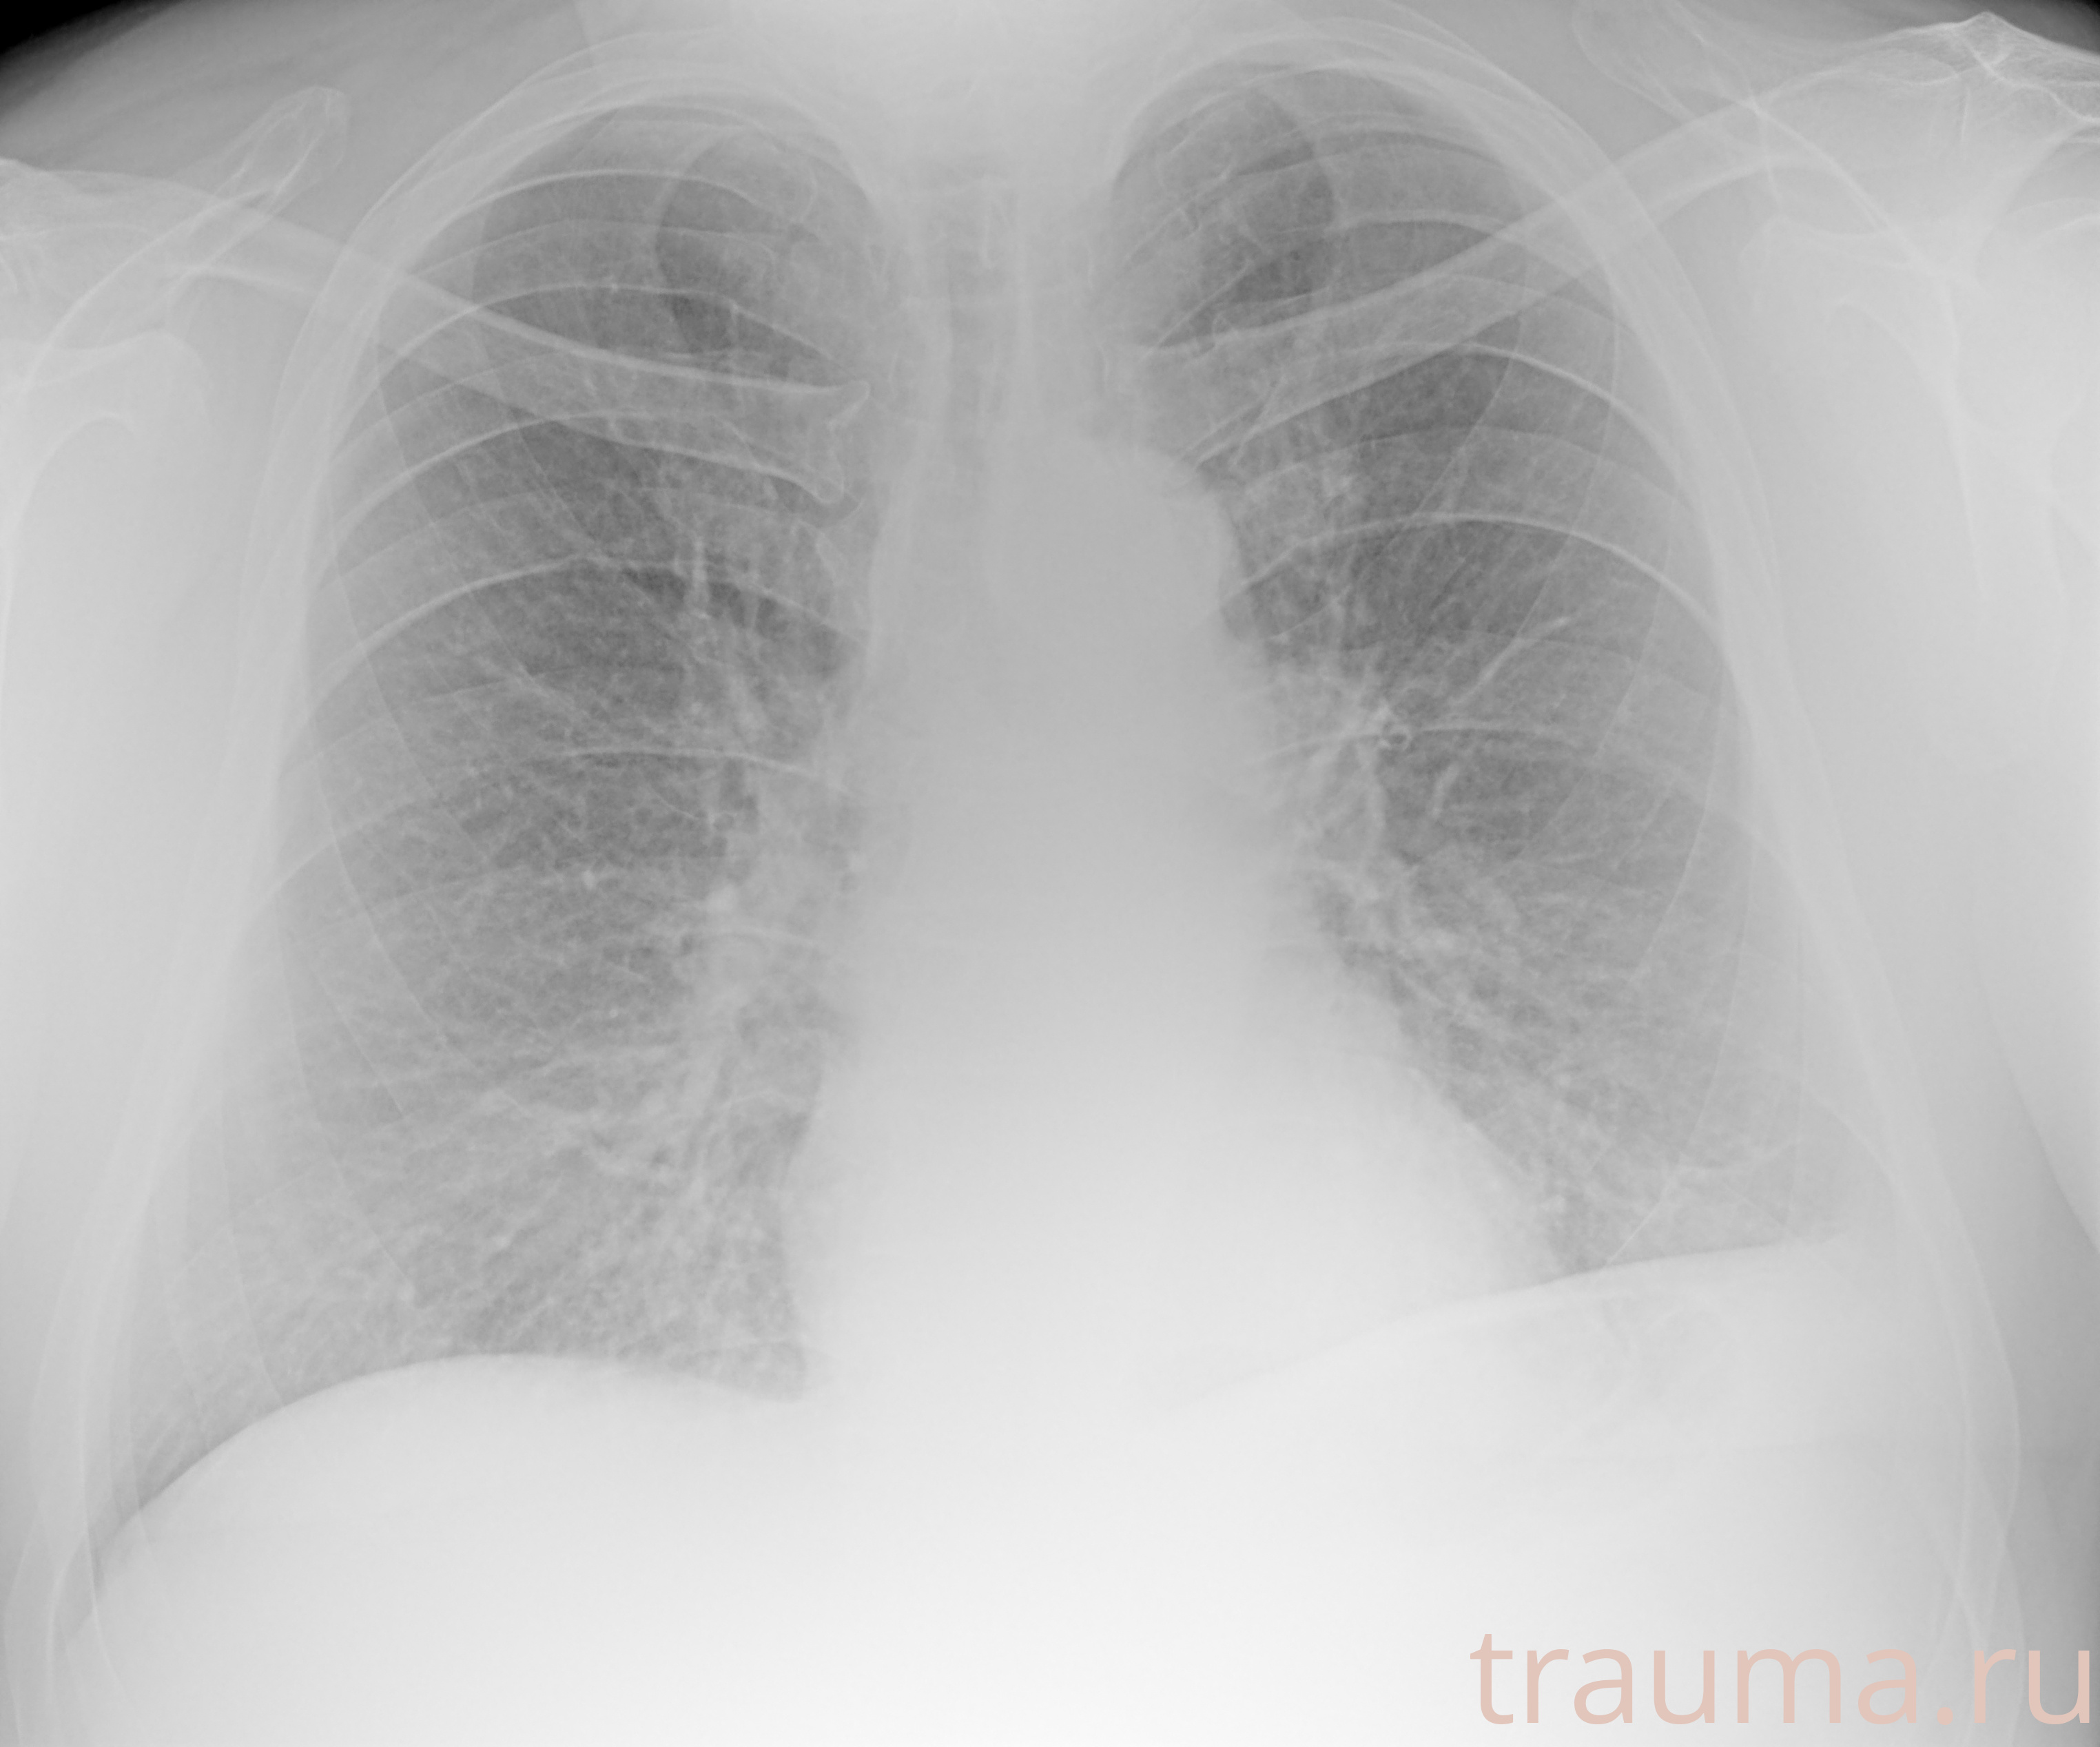

Рентгенограммы

Рентген на дому: по вашему адресу приезжает врач-рентгенолог, травматолог-ортопед с мобильным рентгеновским аппаратом, проводит диагностику травмы или заболевания, делает необходимые рентгенограммы, дает рекомендации по дальнейшему лечению. Получить качественные снимки в домашних условиях возможно благодаря уникальной методике, разработанной МосРентген Центром для института  Склифосовского

при переломе шейки бедра и пневмонии от компании МосРентген Центр - партнера Института имени Склифосовского